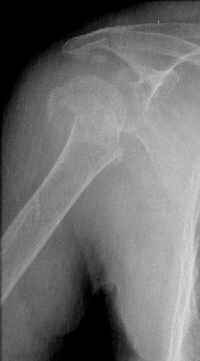

Hello,I am presenting a case of 80 year old male patient right handed known case of hypertension, diabetes and history of CVA 2 years back had a fall in the hosue 10 days back and came to me for pain and ecchymosis around the right shoulder. Xray shows evidence of comminuted fracture proximal humerus extraarticular. He is a doctors father and the doctor wants to know is there any minimally invasive procedure we can do ... I have advised him to go for complete surgery in the form of the AO locking plate under general anesthesia. He is a little reluctant for complete general anaesthesia. My questions to the house is ...1. Is there any other option besides the locking plate ?? (Less invasive) 2. If he is not medically fit for surgery, then can we leave him alone if yes what are the chances of going it into non union? Awaiting your reply Dr Neeraj Bijlani

Another option could be closed nailing, see an example, the surgery was done 2 days ago. In common such surgeries are performed under regional anesthesia, not general.

Fragments now look severely displaced.